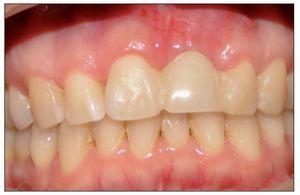

En todos los casos intervenidos mediante ROG en conjunto con injerto conectivo se logró una mejora y equiparación de los contornos periimplantarios con las piezas vecinas u homólogas, en relación con la posición del margen periimplantario y cénit.

No existieron complicaciones posoperatorias, todos los implantes se oseointegraron, y la regeneración de tejidos duros y blandos fue exitosa en todos los casos intervenidos, lográndose una ganancia de ambos tejidos tanto en sentido horizontal, determinado durante la instalación del implante, como también en sentido vertical, comprobado por la posición final del margen periimplantario del implante ya rehabilitado, el cual se situó en una posición más coronal con respecto a la posición original del margen gingival de la pieza dentaria previa a su extracción.

Figura 14.Paciente rehabilitado.

Una vez rehabilitados los implantes, se equiparó la posición del margen gingival, cénit y la relación coronaria con respecto a la pieza vecina u homologa en todos los casos intervenidos.

Al evaluar el grado de satisfacción de los pacientes con respecto a la restauración final, la totalidad de los pacientes indicaron estar altamente satisfechos con su estética y con la integración de la restauración con respecto al resto de las piezas dentarias.